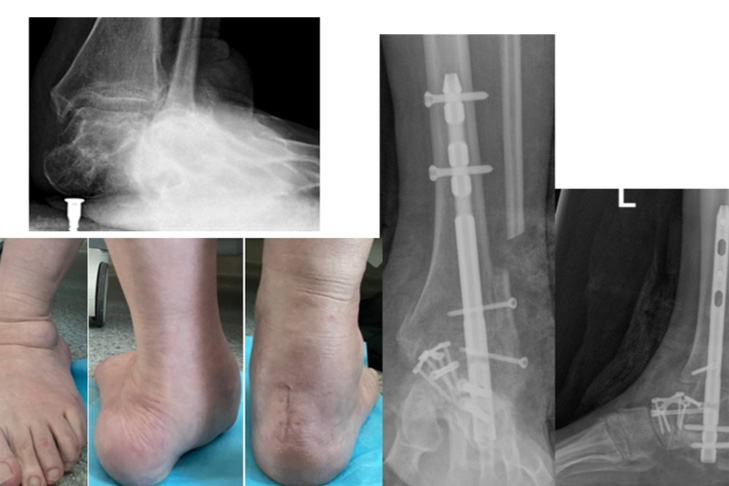

В НИИТО выполнили реконструктивную операцию с восстановлением соотношения костей и фиксацией специальными конструкциями для срастания в правильной позиции. Завотделением, к.м.н. Сергей Гуди, пояснил стандартную схему лечения: «Сначала мы оперируем более поражённую ногу: таков стандарт безопасности. Затем требуется хирургическая пауза, чтобы пациентка восстановилась, научилась ходить на костылях, опираясь на здоровую ногу. Только когда первая стопа уже может служить надёжной опорой, мы оперируем вторую».

По словам врачей, это минимизирует риски и делает реабилитацию комфортнее. В обоих случаях выполняется реконструктивная операция: мы вернули стопе правильное положение и зафиксировали кости при помощи специальных конструкций, чтобы они срослись в нужной позиции.